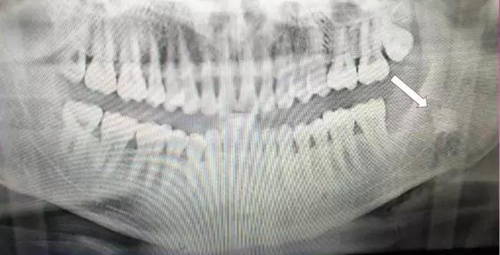

下面看一個病例,患者,女,30歲,因左下頜智齒嵌塞食物后疼痛,至當(dāng)?shù)匮揽平o予拔除,但術(shù)后1個半月,患者自覺拔牙區(qū)一直隱隱疼痛,時輕時重,遂來診。檢查發(fā)現(xiàn),拔牙創(chuàng)口一直未愈合,未見明顯腫脹,拍片發(fā)現(xiàn),拔牙窩內(nèi)顯示高密度斷根影

像,該斷根臨近下頜神經(jīng)管,同時發(fā)現(xiàn)第二磨牙遠中有兩塊高密度影像,疑似殘留骨片或牙片,應(yīng)該是引起疼痛的原因,經(jīng)與患者溝通,采納建議,進行二次拔牙。

用到4號牙挺,避免敲擊拔牙根,稍有不慎,可能會出現(xiàn)牙根移位下頜神經(jīng)管。